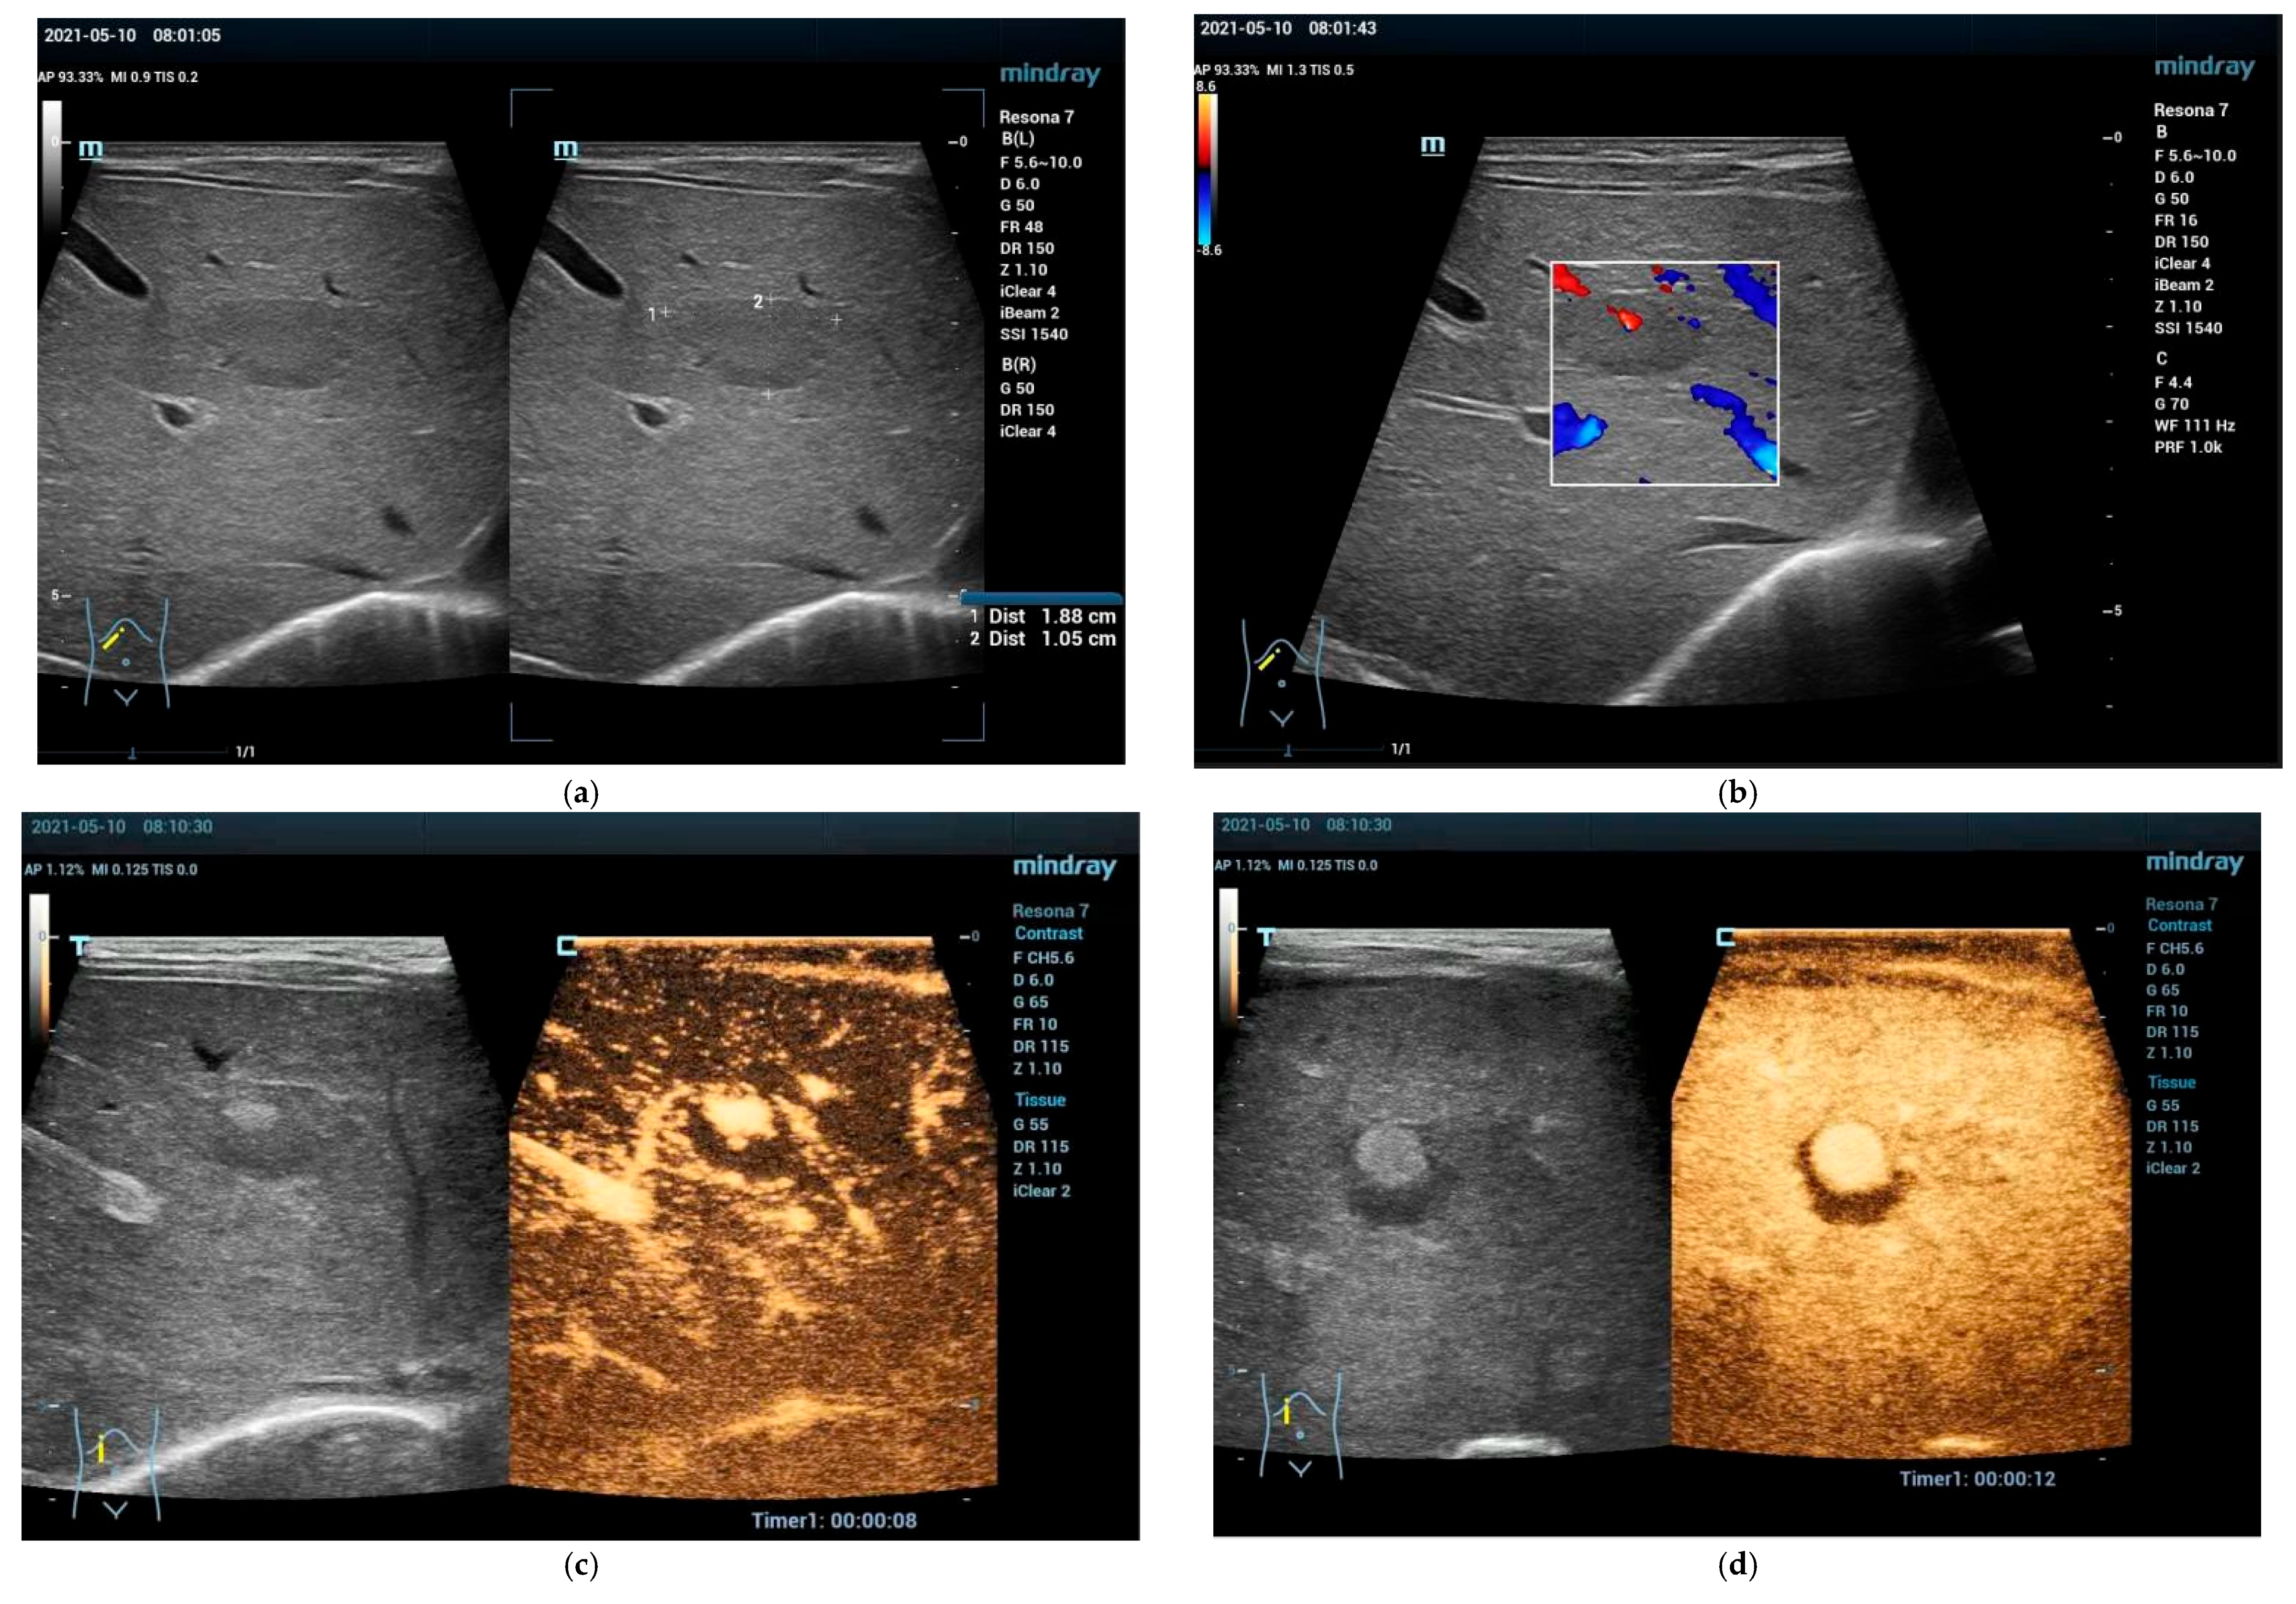

5. Focal Fatty Infiltration and Focal Fatty Sparing (Focal Fatty Lesions, FFL)

5.1. Focal Fatty Sparing (FFS)

5.2. Focal Fatty Infiltration (FFI)